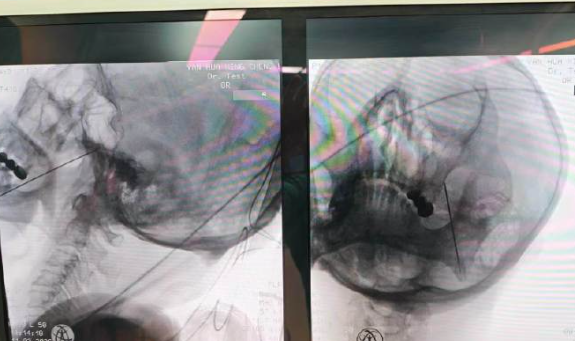

三叉神经半月节射频是目前治疗这类三叉神经痛的优选方式,全程在C臂/CT精准引导下进行,用极细的射频针直达疼痛“总开关”,温和调节受损神经,阻断痛觉信号。